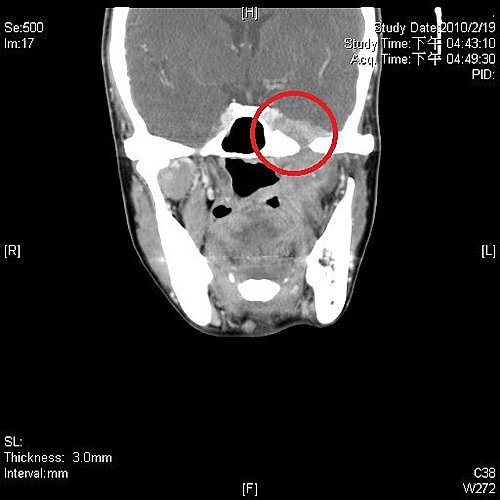

頭部電腦斷層掃描的側面圖。藍圈處為鼻咽部,紅圈處為鼻咽癌已侵入腦底部,

壓迫腦神經。

頭部電腦斷層掃描的正面圖。紅圈處為鼻咽癌已侵入腦底部